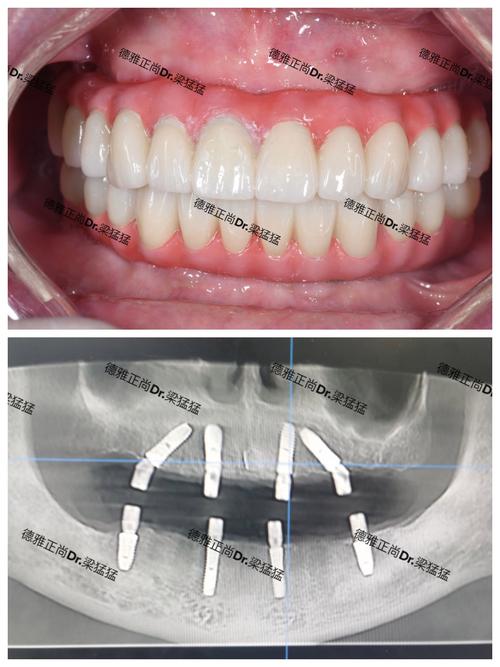

- 案例展示: 要求查看医生的真实种植案例(前后对比照),尤其是与你情况相似的案例,好的医生会很乐意展示。